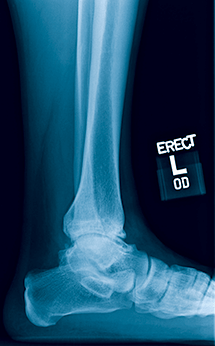

1 and 2

A 55-year-old man had progressive left ankle pain for years. X-rays showed end-stage arthritis with some valgus tilting, but healthy hindfoot joints.